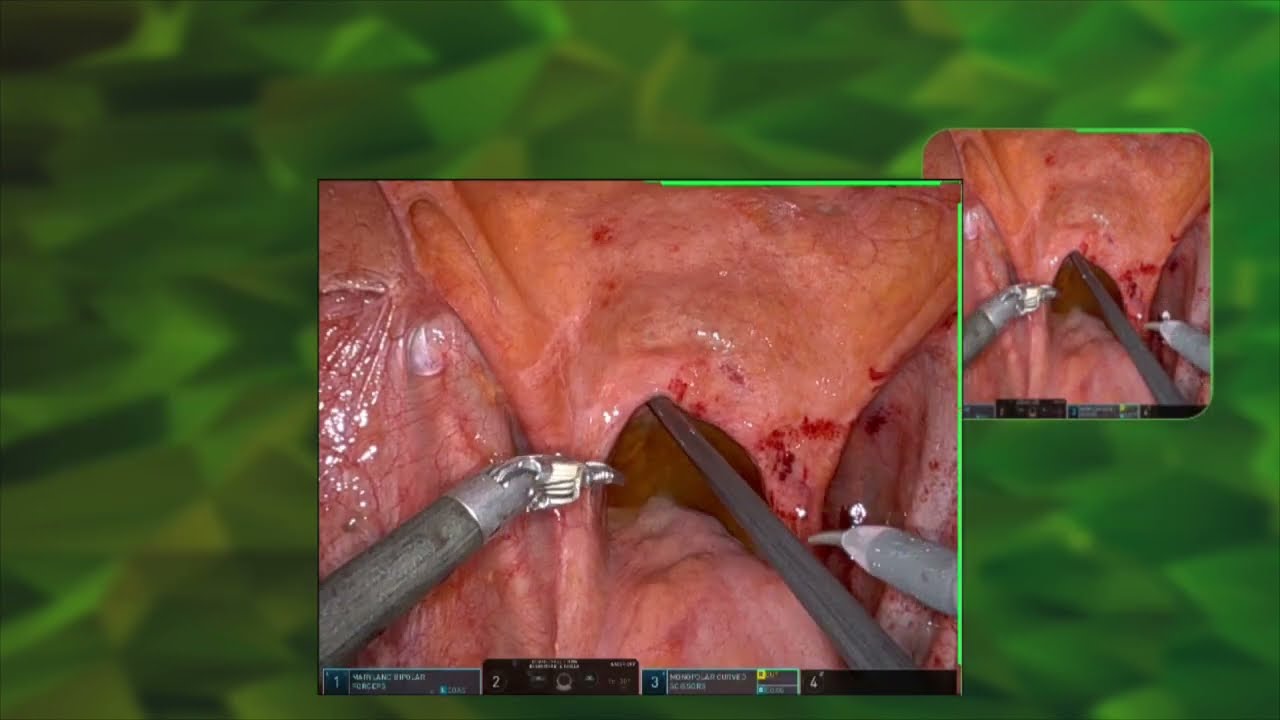

#317 Endopelvic fascia preservation nerve sparing RARP Dr. Kazuhiro Matsumoto

KS Awards, Robotics, Surgeon ';